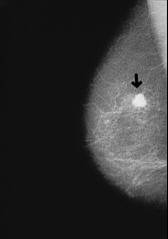

Beispiel: Röntgenbild bei Oberlappen- pneumonie mit Verschattung im mittleren bis oberen Lungenbezirk rechts.

[3] Lungenentzündung (Pneumonie), Röntgenfoto: http://www.doktor.com/krankheiten/lungenentzuendung.html